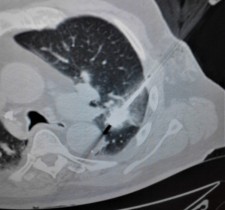

The doctors apply microwave energy to destroy tumors located both centrally and peripherally within the lung using computer tomography (CT) image guidance. The tumors include colorectal cancer, lung adenocarcinoma, thymoma, uterine leiomyosarcoma and ampullary carcinoma in origination. Microwave energy applicators are introduced into the tumors in the lung percutaneously, a minimally invasive technique. A small hole is made through the skin near the tumor location and an applicator is inserted into the lung cavity and lung towards the tumor. Once the positioning of the antenna with respect to the tumor is verified with CT image guidance, microwave energy is applied to the antenna in contact with the tumor to destroy it. The procedures usually take an hour or two depending on the complexity of tumor location and shape to achieve good antenna positioning. The microwave energy application is controlled with direct temperature feedback from the ablation antenna during the procedure to ensure safety and efficacy. Temperature feedback control prevents overheating and runaway conditions and thereby provides the extra safety net for the patients and procedures.

AveCure® microwave ablation system is successfully treating tumors in the lung using a minimally invasive technique. The microwave ablation antenna is introduced through a percutaneous chest wall incision in the skin to access the tumor past the lung cavity and patient is left with a small hole in the skin which quickly heals with almost no scar after the procedure. AveCure® system utilizes a smart antenna in either probe or catheter format and microwave energy controller to select the correct size, temperature and timer settings appropriate for safe, effective and predictable treatment.